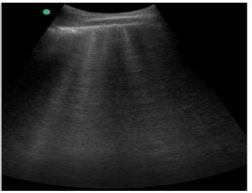

Caso clínico para responder à questão.

Um paciente de 50 anos de idade encontra-se, internado na UTI por conta de choque séptico de foco pulmonar, em ventilação mecânica na modalidade pressão e no modo assisto-controlado. Pela manhã foi submetido a acesso venoso central em veia axilar guiado por ultrassonografia. Ao exame físico, notou-se que o paciente está com hipotensão e taquicardia. A primeira hipótese diagnóstica é pneumotórax e é realizada radiografia com imagem apresentada.